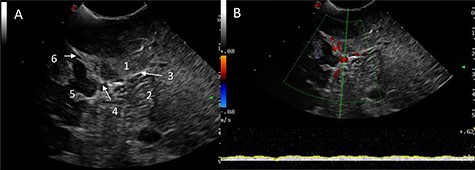

Power and colour Doppler were used throughout to obtain real-time information about the location and function of dural venous sinuses. Blood flow was preserved in the sinuses and, as we debulked the tumour, we were able to demonstrate bi-directional flow within the sinuses (Fig. 3). This suggested resolution of venous obstruction and indicated the dural venous sinuses had regained their functionality. Medially tumour was found invading the torcula and right transverse sinus, and a decision was made to leave the residual tumour and to preserve the sinuses (Fig. 4). We achieved a Simpson Grade 4 resection without any intraoperative complications.

Intraoperative images at the end of resection; Duplex US images (2D image with overlay of colour Doppler) of the initial appearances of the straight sinus (A) and appearance at the end of resection (B); a bidirectional flow in the straight sinus is apparent after tumour resection, this was not present prior to tumour debulking; the Triplex Doppler confirms the bidirectional flow in the straight sinus (C and D).